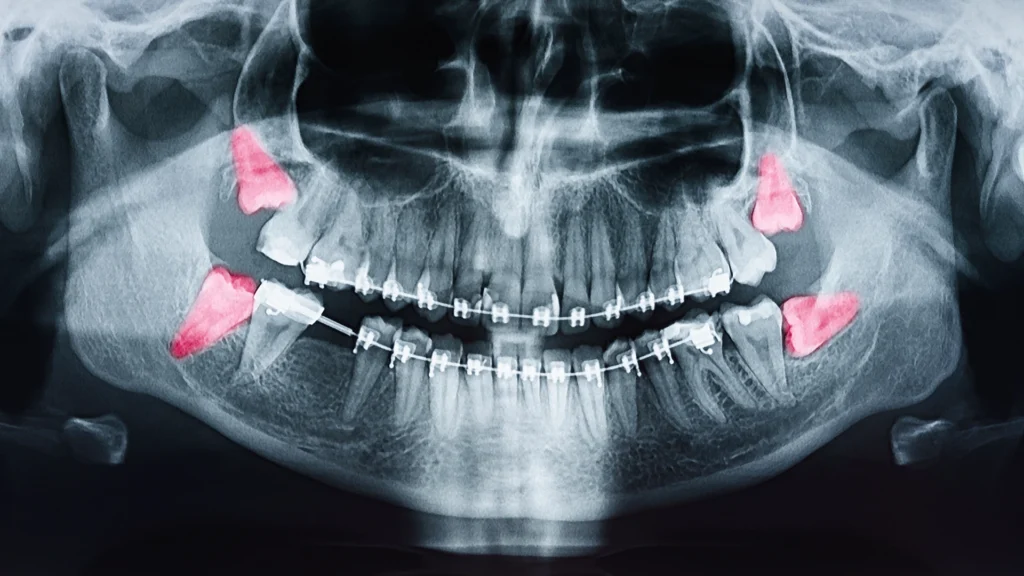

Az evolúció sajátos tréfája ez a fogtípus. Őseink masszív állkapcsában még fontos szerepet töltött be a kemény, nyers ételek őrlésében. A táplálkozási szokások megváltozásával, a hőkezelt ételek elterjedésével az emberi állkapocs mérete fokozatosan csökkent. Ma már a legtöbb embernél egyszerűen nincs elegendő hely a fogsor végén ennek a négy fognak. A helyhiány az, ami a problémák gyökerét adja. A bölcsességfog gyakran nem tud szabályosan előtörni, megreked az állcsontban, vagy csak részlegesen bújik ki az íny alól. Amikor a fog nem a megfelelő irányba, például ferdén vagy vízszintesen próbál utat törni, nyomást gyakorolhat a szomszédos, már stabilan beállt második nagyőrlőre, ami a teljes fogsor torlódásához vezethet.

A szájsebészeti beavatkozás szükségessége akkor merül fel, ha a bölcsességfog nyomja a szomszédos fogat, veszélyeztetve annak épségét vagy a teljes fogsor esztétikáját és funkcióját. Amennyiben nem tud normálisan előtörni, és a ciszta, a tályog vagy a krónikus gyulladás kialakulásának veszélye áll fenn.

Még ha részben ki is bújt, a hátsó pozíciója miatt az alapos tisztítás lehetetlen, ami szuvasodáshoz vezet, ez pedig könnyen átterjedhet a mellette lévő fogra is. A sikeres fogszabályozáshoz, vagy a már elért eredmény megtartásához elengedhetetlen a feszültséget okozó fog eltávolítása.